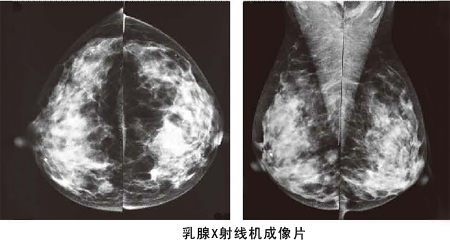

乳腺癌發現越早,治療效果越好。所以應該每年到體檢中心,做一次乳腺專科檢查,這是非常有必要的。建議25歲以后的女性定期乳腺檢查,35歲以上每年一次B超,40歲以后每1~2年進行一次鉬靶X線檢查

鉬靶X線

鉬靶X線則是目前乳腺疾病檢查、發現和診斷早期乳腺癌的有效手段。BTX-9800A型鉬靶X線機采用現代科學技術,自動化程度高,圖像清晰;人性化的設計使操作極為方便,成為乳腺疾病影像學診斷中的重要設備。